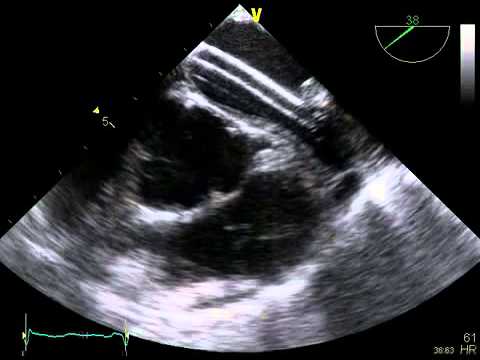

Video 7.1

Video 7.1 Bicaval view from transesophageal echocardiography showing the atrial septum.